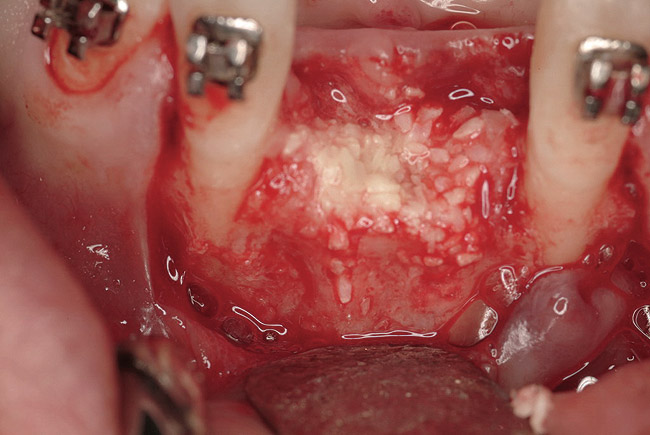

Figure 16  The edentulous anterior sextant. Portions of the facial bony wall remain in the maxillary left central and lateral incisor region. The long-standing abscess associated with tooth Nos. 7 and 8 has resulted in total loss of the bony plate in this area.

Figure 16

Figure 17  The extraction sites of tooth Nos. 9 and 10 were obturated with rhBMP-2/ACS. The presence of a portion of the facial cortex provided space maintenance for bony regeneration. The same biomaterial was placed into site Nos. 7 and 8, but a resorbable PLGA mesh was contoured over the site and fixed to the facial bone to provide regenerative space in this area.

Figure 17